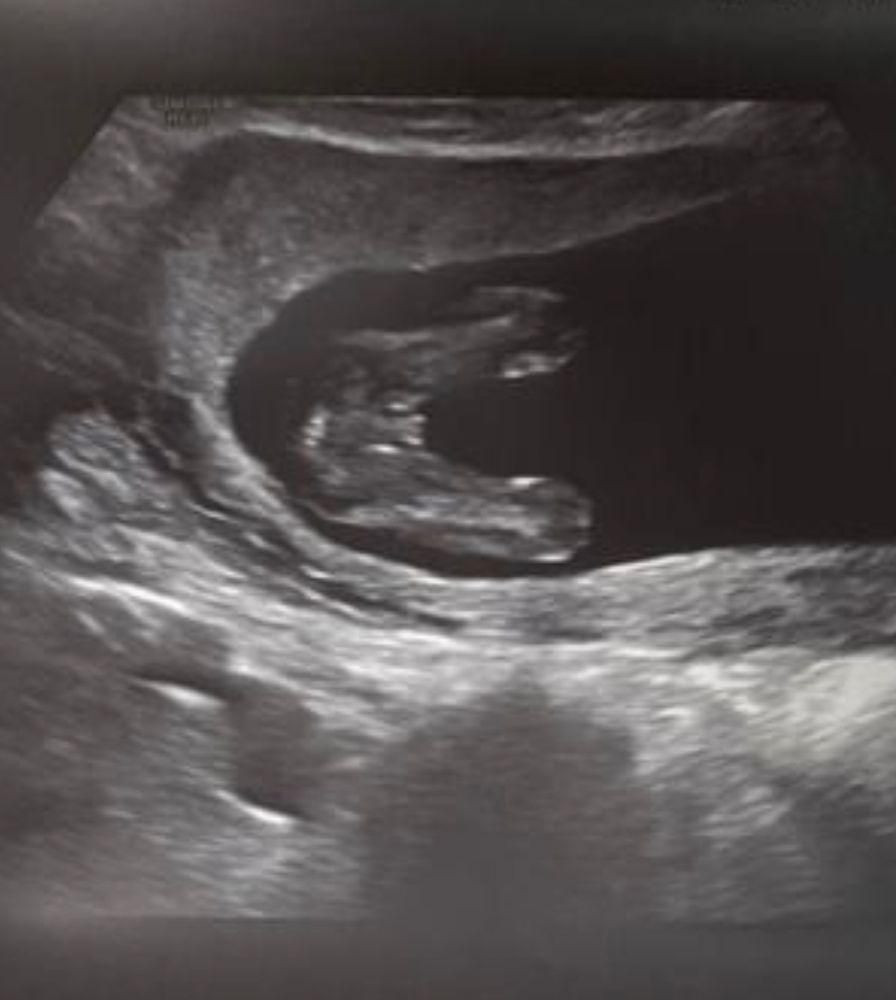

Девочки помогите 🆘 мальчик или девочка ? До 30 недель 4 разных врача утверждали что девочка ,узи на 17 неделе , а тут пошла на допплер и врач говорит что мальчик 👦 мы уже все вещи розовые купили 😅было ли у кого такое ? 30 недель снимок также прикладываю

У меня в 14 недель говорили девочка, тоже покупала вещички 😅 а в 17-19 уже мальчик. Тоже была в шоке , до сих не верится